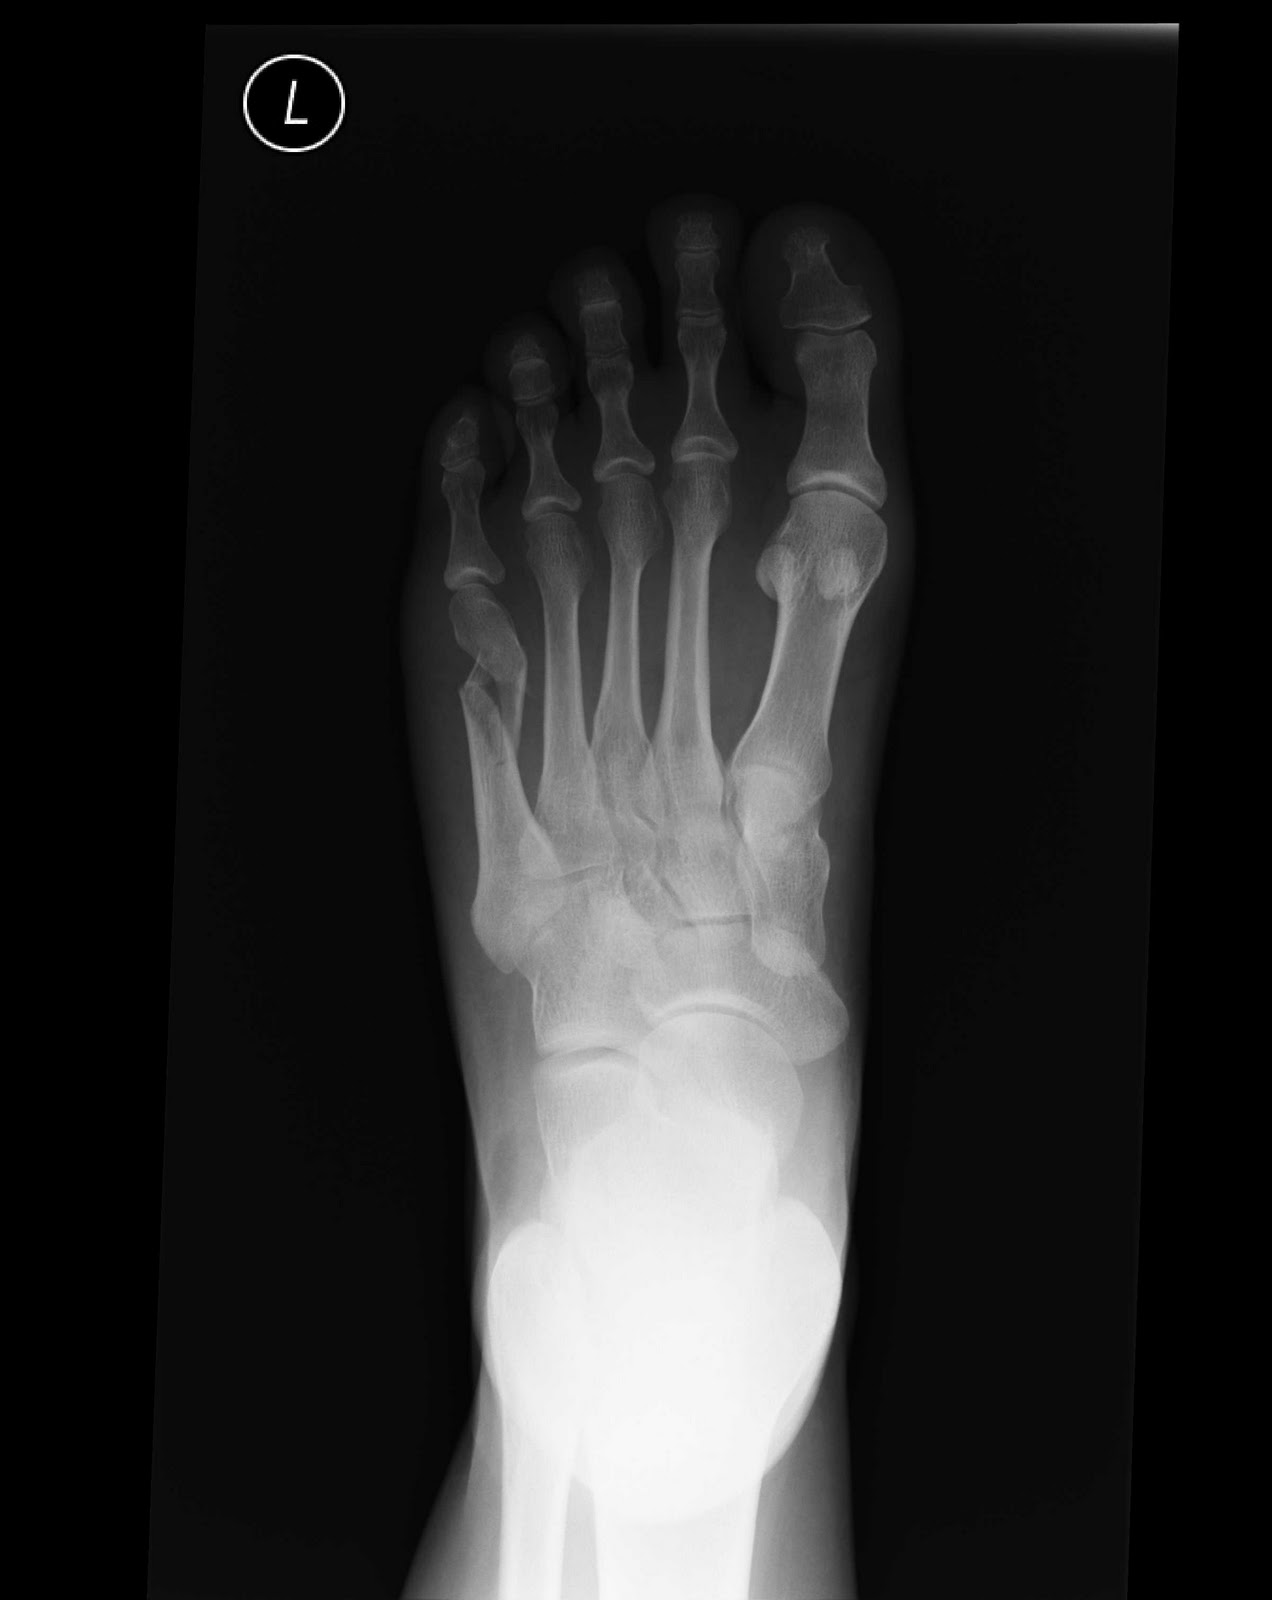

A metatarsal fracture is when one of these bones is broken. Show additional info hide additional info.

Fractures to the metatarsal bones can be caused by direct trauma, excessive rotational forces or overuse. It includes updates that came into effect between 1998 and 2010, as well as the corrigenda to volume 1, which appeared as an. Avulsion fracture of the base of the fifth metatarsal not seen on conventional radiography of the foot:

International statistical classification of diseases and related health problems. Read about causes, treatment options, available mobility devices, recovery timeframes, & more. Metatarsal fractures represent a significant proportion of foot injuries. A metatarsal fracture is when one of these bones is broken. Fractures of proximal portion of fifth metatarsal bone: First, followed by a code from m84.5 for the pathological fracture. 68% associated with fracture of 2nd or 4th metatarsal. Avulsion fracture of the base of the fifth metatarsal not seen on conventional radiography of the foot: More than 30 minutes may damage the skin.) make an ice pack by wrapping ice cubes in a plastic bag or towel. The information provided is only intended to be a general summary and not intended to take place of either written law or. Metatarsal fractures may occur via direct trauma, overuse, or inversion injuries. Displaced 1st metatarsal fracture= orif, generally fixed with plates/screws. Various patterns of metatarsal injuries exist and the resultant impact on function and quality of life is not negligible. Transverse fracture at the base of the fifth metatarsal in a male the first metatarsal is injured in 10% of metatarsal stress fractures; Fractures of the proximal fifth metatarsal pose an important diagnostic challenge. Distal radius fractures programme online course: Fractures to the metatarsal bones can be caused by direct trauma, excessive rotational forces or overuse.